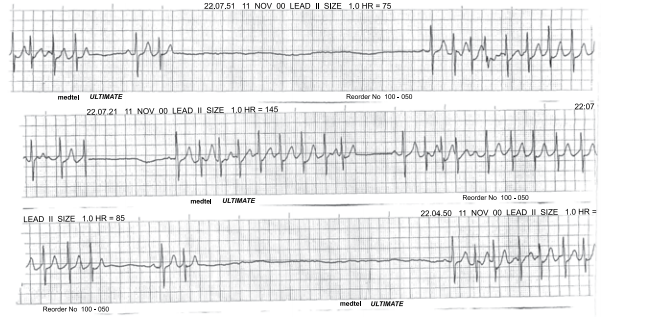

Leia o enunciado a seguir e responda a questão.

Paciente do sexo feminino, 66 anos, com antecedentes de tabagismo, hipertensão arterial sistêmica e diabetes mellitus tipo 2, procura atendimento médico com queixa de desconforto retroesternal tipo queimação e opressão que se iniciou há 1 mês, desencadeado aos grandes esforços. Há 1 semana passou a apresentar os mesmos sintomas em repouso, associados à dispneia, com duração de até 8 minutos e melhora espontânea. A paciente faz uso de valsartana 80 mg, glimepirida 4 mg e metformina 1000 mg. O exame físico é normal, PA = 150x85 mmHg e frequência cardíaca de 96 bpm. O eletrocardiograma está ilustrado a seguir.

Provas

Homem, 46 anos, com antecedente de infarto agudo do miocárdio, é portador de miocardiopatia isquêmica e insuficiência cardíaca. Atualmente recebe tratamento otimizado para insuficiência cardíaca, no entanto permanece em classe funcional III (NYHA). O ecocardiograma mostra diâmetro diastólico do ventrículo esquerdo = 72 mm e fração de ejeção do VE = 34%. Holter de 24 horas: extrassístoles ventriculares frequentes, quatro episódios de taquicardia ventricular não sustentada e um episódio de taquicardia ventricular sustentada com 1 minuto de duração. O eletrocardiograma está ilustrado a seguir.

Assinale a alternativa correta em relação à redução de morbimortalidade do paciente em questão.

Homem, 77 anos, hipertenso e diabético, em uso regular de losartana, hidroclorotiazida e metformina, queixa-se de palpitação e pré-síncope nos últimos 3 meses. O exame físico é normal e o ecocardiograma mostra função biventricular preservada e ausência de alterações da contratilidade segmentar. O eletrocardiograma dinâmico, durante exacerbação dos sintomas, está apresentado a seguir.

Assinale a alternativa que contém o diagnóstico e a conduta terapêutica correta.